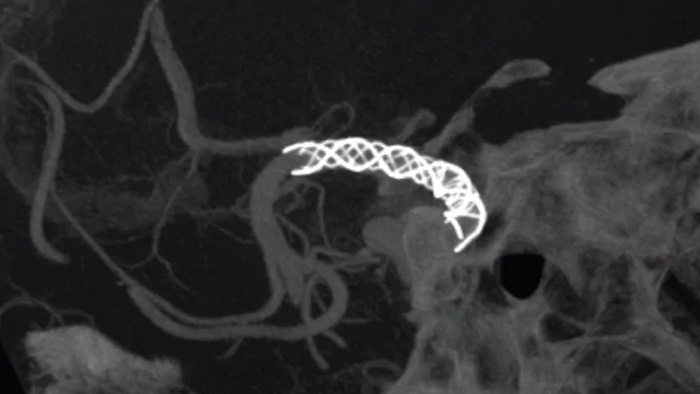

Vea claramente los perforadores cerebrales y los dispositivos desafiantes

SmartCT Vaso IA

Mejorar la vista de los stents endovasculares, los diversores de flujo y otros dispositivos, así como la morfología de los vasos hasta el nivel del perforador con SmartCT Vaso. Esta técnica de adquisición se basa en una exploración por TC de haz cónico y una inyección de contraste intrarterial. Se utiliza cada vez más para el seguimiento de aneurismas tratados con diversores de flujo para comprobar la posición del dispositivo.